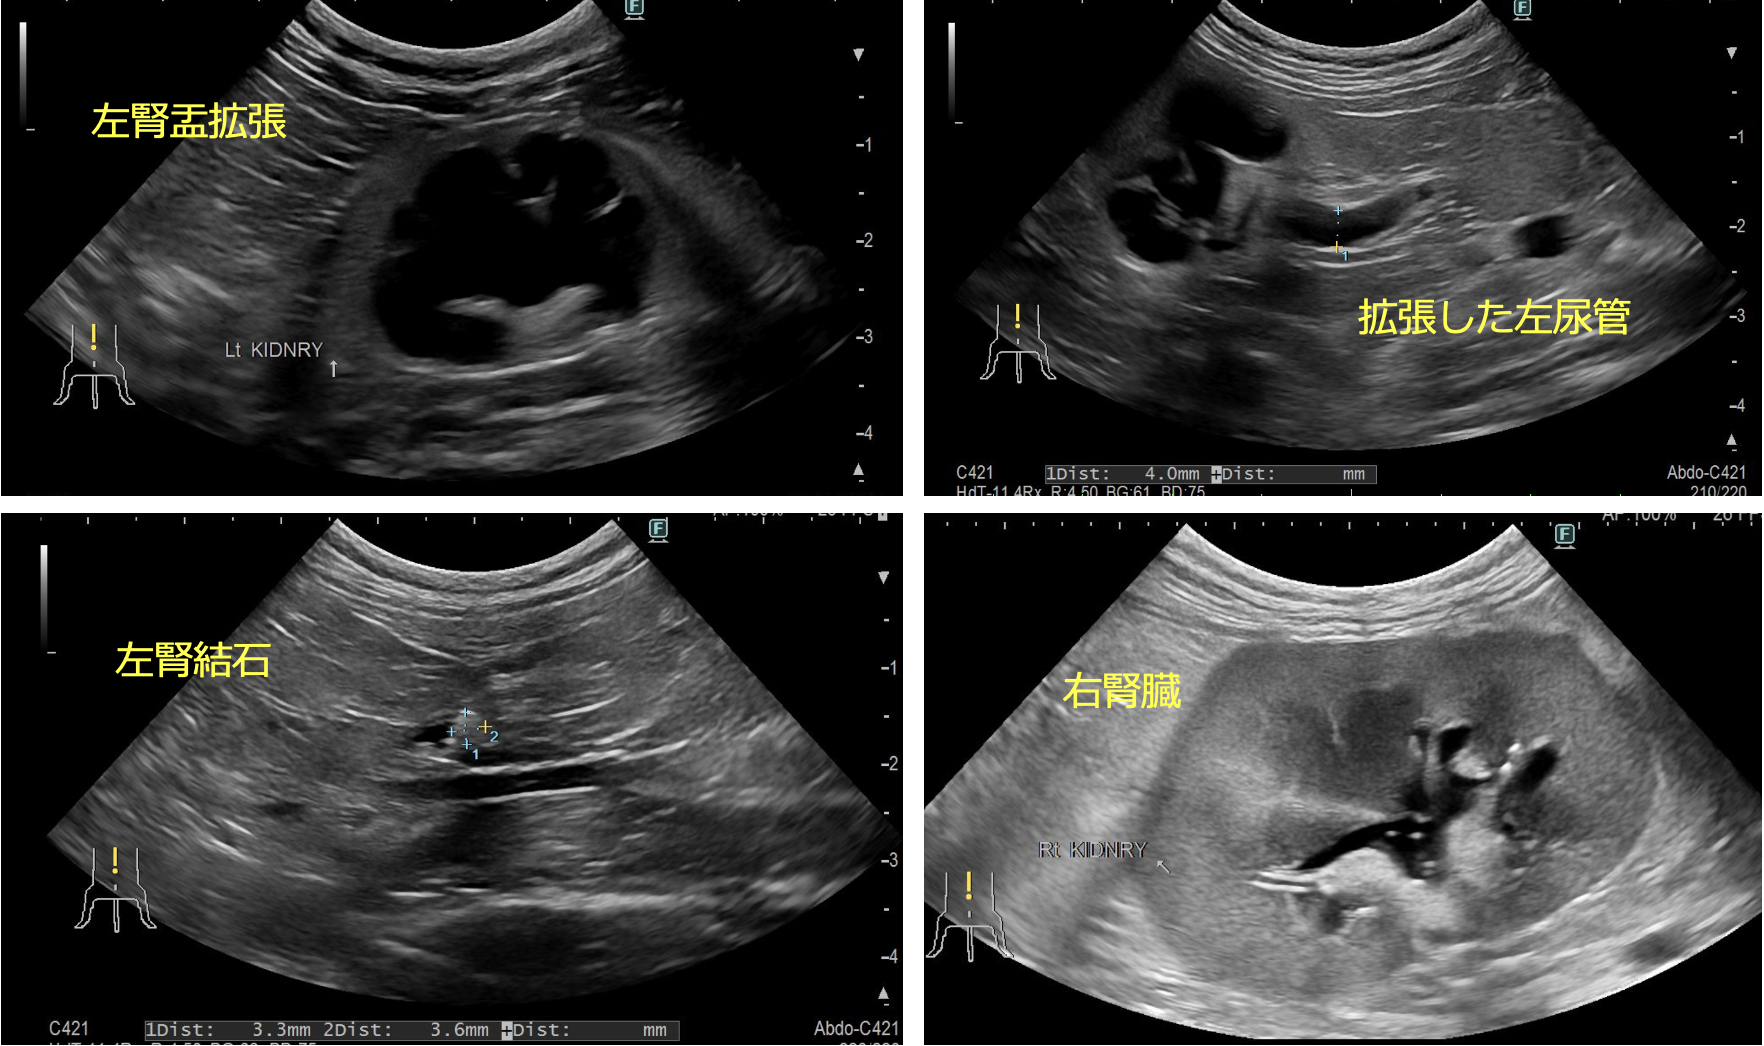

レントゲン、CT検査より左右の尿管に結石が認められた。また左腎臓腎盂の拡張が認められた。